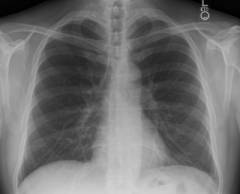

| Поражение легких |

|

| Поражение легочных артерий, которые несут венозную кровь к легким. |

- симптомы поражения легких;

- Ограниченный: поражение захватывает верхние дыхательные пути и легкие. При этом сосуды почек не страдают.